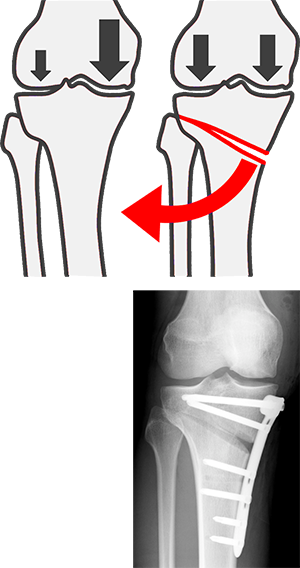

Idealerweise sollte das Bein mehr oder weniger gerade sein (eine mäßige X-Beinstellung [valgus], insbesondere bei Frauen, ist normal). Exakter ausgedrückt: Das Kniegelenk sollte in der Kraftlinie zwischen Hüftkopf und Sprunggelenk liegen. Kommt es zu Abweichungen dieser Achse, so resultiert eine Fehlbelastung. Im Folgenden beschränke ich mich auf das O-Bein [genus varum]. Hier wird der innere Anteil des Kniegelenkes mehr belastet als der äußere (schwarze Pfeile im Bild). Das wird ganz offensichtlich, wenn man im Stehen das Knie nach außen drückt, also eine O-Bein Stellung simuliert: Der Druck innen nimmt zu.

Leider reicht das oft nicht aus. Dann ist der Knochen umzustellen. Man kann das erreichen, indem man den Schienbeinkopf durchtrennt und den so entstandenen Spalt außen aufklappt. So macht man aus dem O-Bein ein leichtes X-Bein [valgisierende Tibiakopf-Osteotomie]. Der verbleibende Knochenspalt im Schienbeinkopf wird mit einer Platte und Schrauben fixiert.